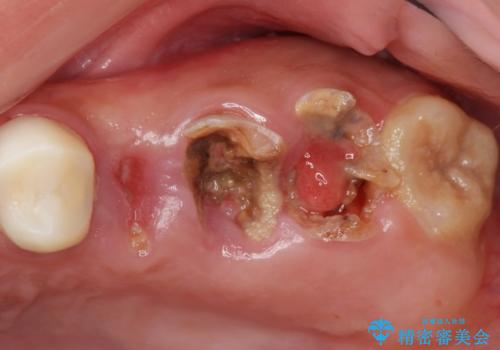

![[親知らずの移植] インプラントを用いない咬合回復の症例 治療前](https://seimitsushinbi.jp/wp/wp-content/uploads/2017/09/dcee39cf917a7a352bc6fcb0183543af-500x350.jpg)

![[親知らずの移植] インプラントを用いない咬合回復の症例 治療後](https://seimitsushinbi.jp/wp/wp-content/uploads/2017/09/609c83174eb270ca046e1500a1298cd6-500x350.jpg)